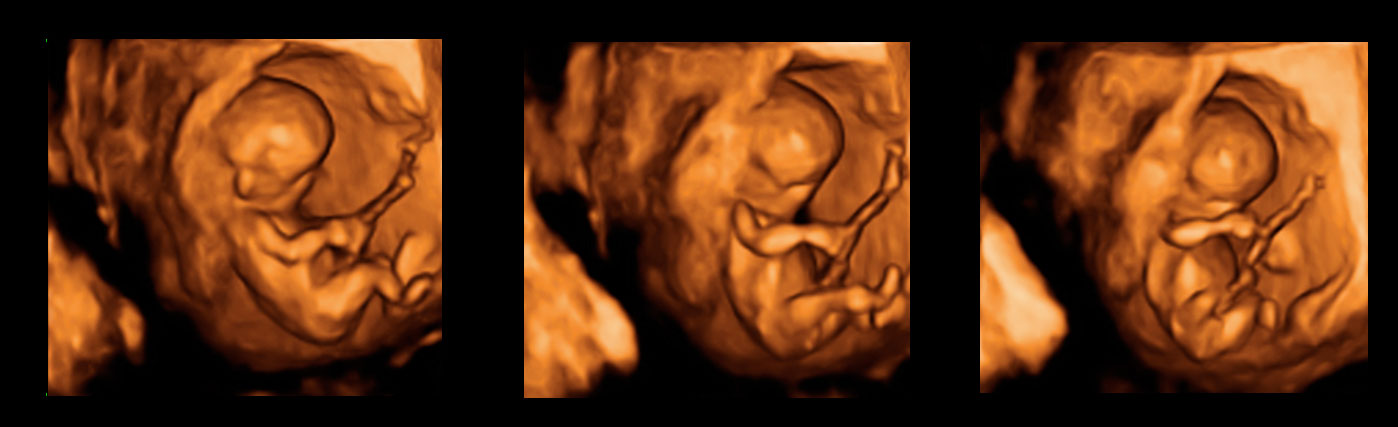

Ecografía 3D de la semana 12: Feto de perfil

Cabeza, tronco y extremidades son claramente visibles

En la imagen podemos ver un feto de 12 semanas en una ecografía tridimensional. Se pueden observar con nitidez el cordón umbilical y las paredes uterinas. También, las estructuras básicas del bebé como cabeza, tronco y extremidades. A estas alturas de gestación, el niño presenta un aspecto muy parecido al de un recién nacido, a falta de la maduración completa de sus órganos.

Ecografía 3D: Feto de perfil de 12 semanas